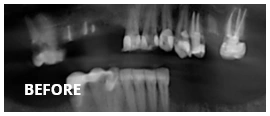

However, we are the team to see when your mouth is in need of major work. We are the dental specialists with the advanced training and years of experience required to solve the big problems. We do not judge. We simply provide proven solutions that work.